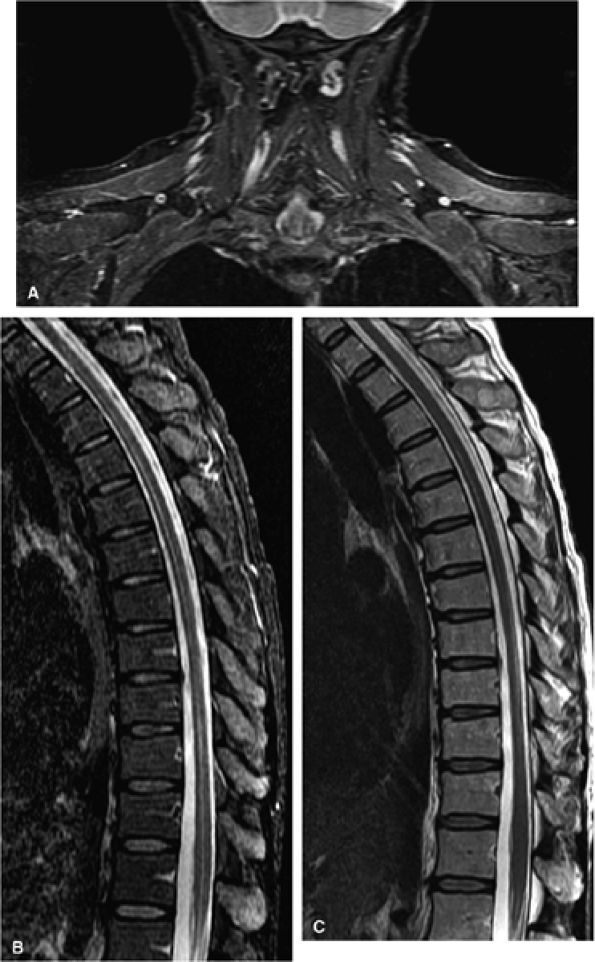

FIGURE 1.13 ● STIR imaging with a large FOV improves image quality in challenging areas such as (A) the brachial plexus and (B) the spine. (C) T2-weighted image for reference. In such applications, chemical fat saturation may show uneven fat suppression.